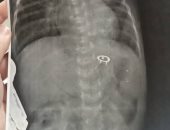

فريق جراحى بمستشفى ناصر التخصصى ينقذ رضيع عمره 14 يوماً من جسم غريب فى معدته

نجح فريق جراحي بقسم الأطفال المبتسرين بمستشفي ناصر التخصصي بشبرا الخيمة بمحافظة القليوبية، والتابعة لأمانة المستشفيات المتخصصة، في إنقاذ حياة رضيع